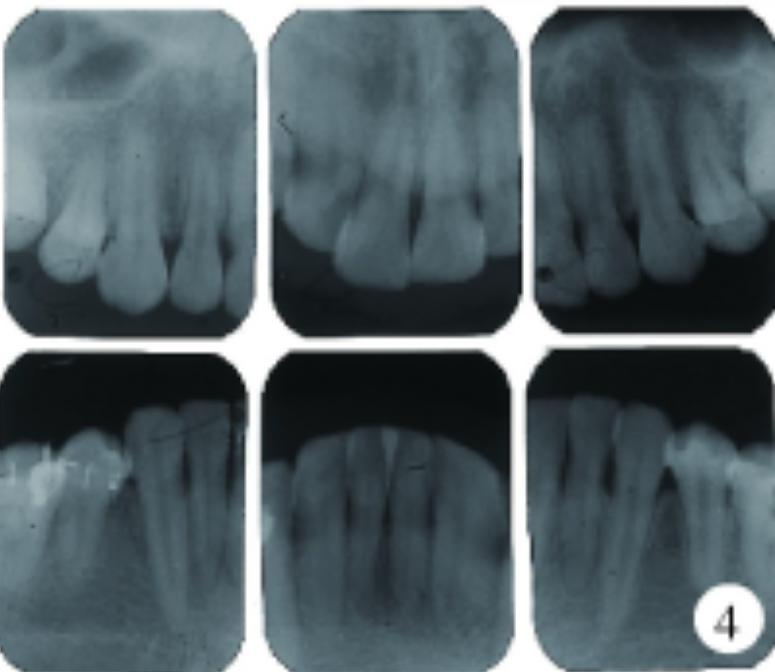

牙周探诊深度(probingdepth,PD)普遍4~7mm,中等量菌斑,探及大量龈下牙石,探诊出血74.0%。全口根尖片显示普遍的牙槽骨轻度吸收。

图4.jpg